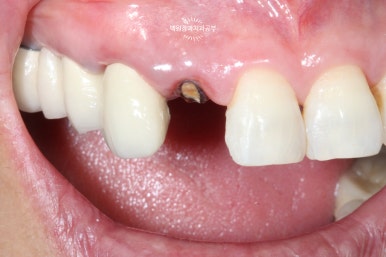

오른쪽 위 가쪽 앞니 (측절치)가 뿌리만 남아있는 것을 보실 수 있을겁니다. (잔존 치근)

대부분.. 아니 거의 100이면 100 일반 치과에서 발치 즉시 임플란트를 권하게 됩니다.

키워드는 '건전한 치아 뿌리'와 '뿌리가 하나인 치아'

외과적 정출술 - 이를 의도적으로 뽑고 '덜' 집어 넣습니다.

왼쪽: periotome을 사용하여 발치 시행, 오른쪽: 치아를 완전히 뽑지 않고 위치를 수정.